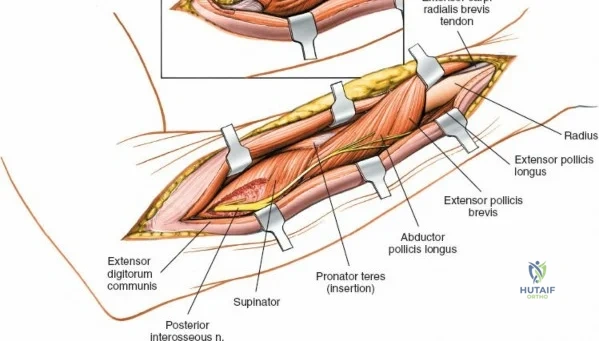

Deep Surgical Dissection: Exposing the Proximal Third

Exposing the proximal third of the radius requires extreme vigilance due to the proximity of the posterior interosseous nerve. The key anatomical landmark here is the insertion of the biceps tendon. Follow the biceps tendon distally to its insertion on the bicipital tuberosity of the radius. A small bursa lies just lateral to the tendon; incise this bursa to gain initial access to the proximal radial shaft. Because the radial artery lies superficial and medial to the tendon at this level, all deep dissection must remain strictly lateral to the biceps tendon.

The proximal radius is draped by the supinator muscle. The PIN passes directly through the belly of the supinator. To protect the nerve, the forearm must be fully supinated. Supination dynamically rotates the radius, carrying the insertion of the supinator anteriorly and simultaneously displacing the PIN laterally and posteriorly, safely away from the surgical field.

With the forearm fully supinated, identify the broad insertion of the supinator on the anterior aspect of the radius. Incise the supinator directly along the line of its insertion onto the bone. It is critical to detach the muscle by dividing its insertion sharply at the bone, rather than splitting the muscle belly, which would risk cutting the PIN.

Proceed with strict subperiosteal dissection, elevating the supinator laterally off the bone. This is one of the rare instances in orthopedic surgery where the safety gained by staying in a subperiosteal plane completely outweighs the theoretical vascular damage to the bone caused by periosteal stripping. The elevated supinator muscle belly now acts as a protective cushion for the PIN.

Retractor Placement and Fixation Technique

Once the proximal radius is exposed, great care must be taken with retractor placement. Never place Hohmann or levering retractors blindly around the posterior surface of the radial neck. Because the PIN may touch the bone posteriorly in up to 25% of patients, a posteriorly placed retractor can easily crush the nerve against the radial cortex. Instead, use gentle right-angle retractors or place retractors only on the anterior and lateral aspects of the bone, utilizing the elevated supinator as a shield.